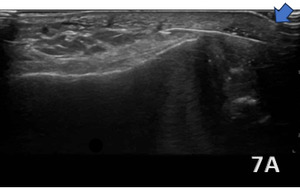

ACHILLES INSERTIONAL TENDINOPATHY

Figure 7A (LAX View):

Insertional Achilles tendinopathy (blue arrow highlighting) is characterized by pathological changes in the distal 2 cm of the Achilles tendon at its attachment to the calcaneus. On diagnostic ultrasound, hallmark findings include tendon thickening and hypoechoic areas indicative of collagen degeneration and disorganization. Calcifications or enthesophytes at the insertion site are common and appear as hyperechoic foci with posterior acoustic shadowing. Associated retrocalcaneal bursitis may be visualized as an anechoic or hypoechoic fluid collection between the anterior Achilles tendon and the calcaneus, with possible synovial hypertrophy in chronic cases. Power Doppler imaging may reveal hypervascularity at the tendon insertion, reflecting a chronic inflammatory response.